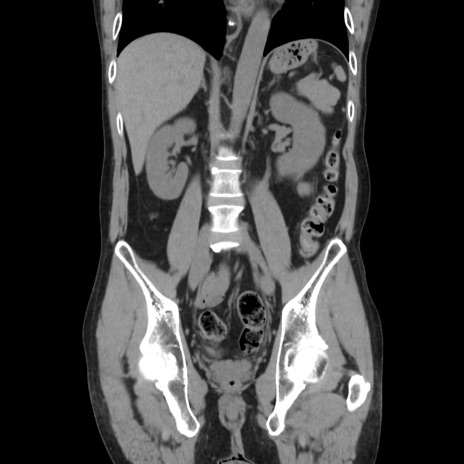

症例37(冠状断像)

【症例】40歳代 男性

【主訴】腹痛

【現病歴】4時間ほど前に電車に乗車中に臍部上より腹痛出現。徐々に増悪し起立困難となり、救急外来受診。生ものは数日食べていない。今朝お雑煮を食べた。

【身体所見】BT 36.8℃、BP 117/84mmHg、HR 91/min、SpO2 97%、苦悶様、腹部:臍上部広範囲圧痛あり、反跳痛±

【データ】WBC 8100、CRP 0.03